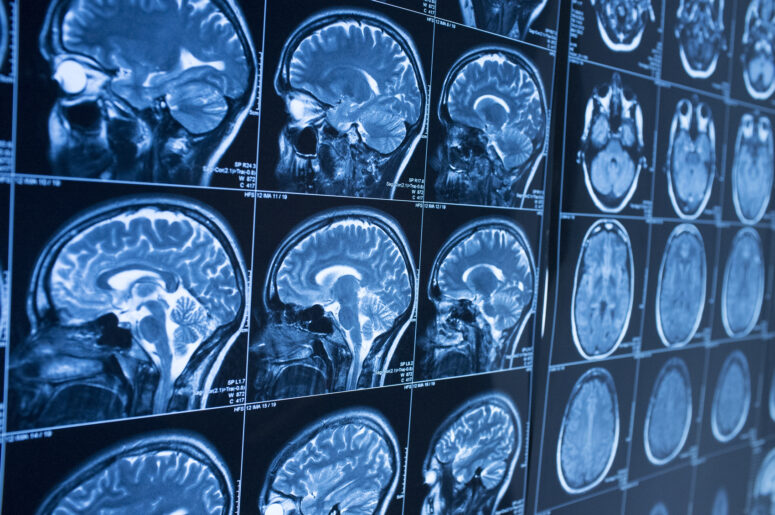

Two years ago, the man, then 28, sustained a traumatic brain injury after he was thrown from his SUV in a rollover accident after a tractor-trailer rig cut him off in traffic. Doctors warned his family that he might not regain consciousness or be able to move again, let alone walk on his own, if he did wake up.